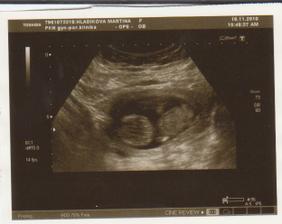

NT screening 12+4tt

1. velké měřeníčko